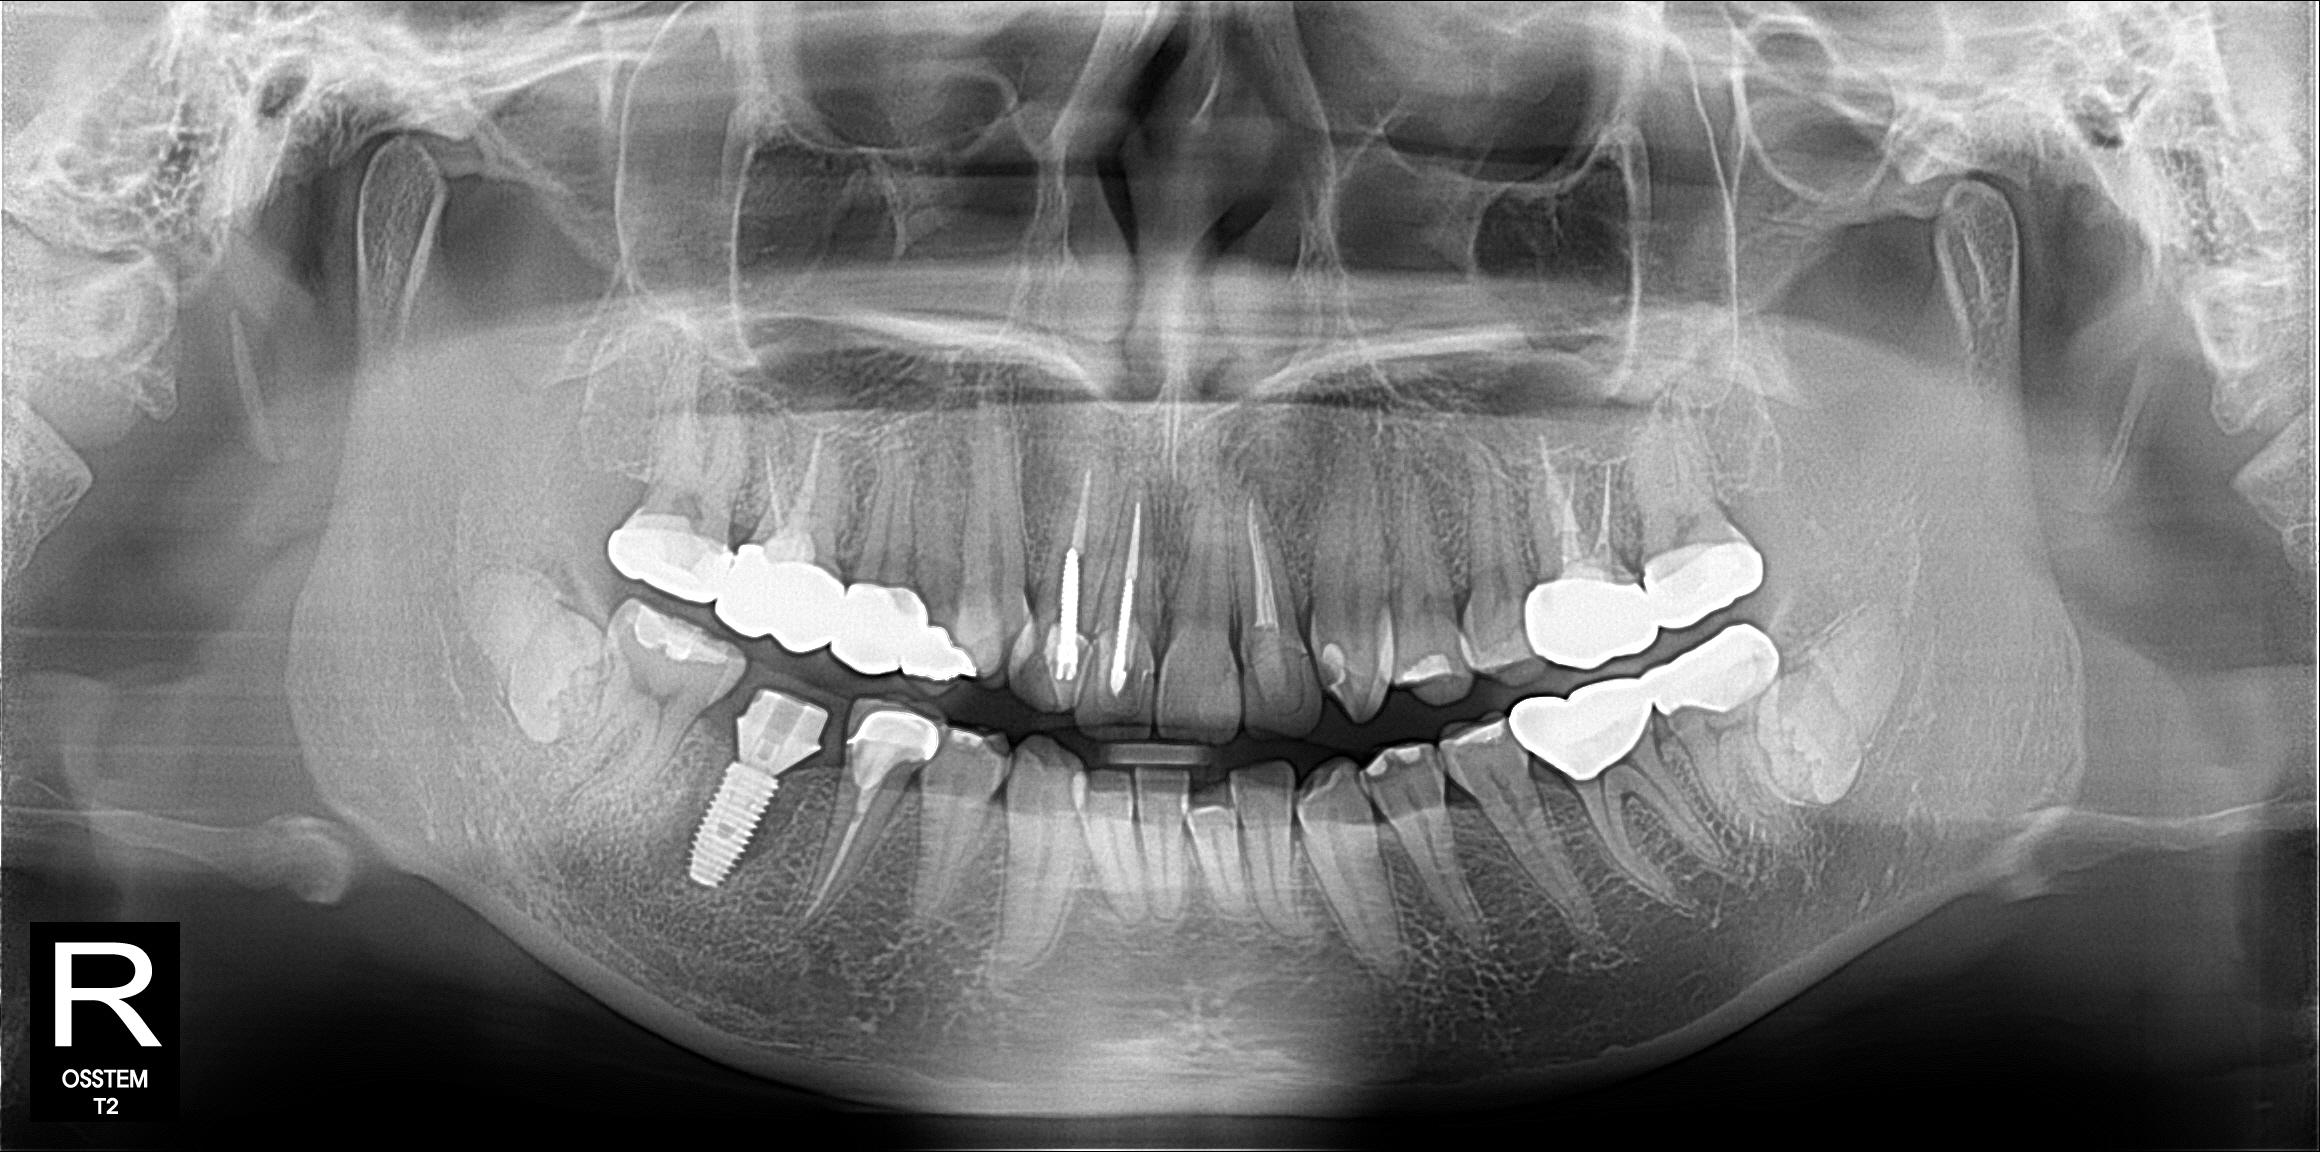

Your dentist examines your mouth and takes X-rays or a CBCT scan to assess your bone levels, gum health, and the gap area. Together, you review your options and create a treatment plan.

OPG panoramic X-ray used to assess bone levels and plan tooth replacement at Trust Dental Surgery

Usually 30–45 minutes